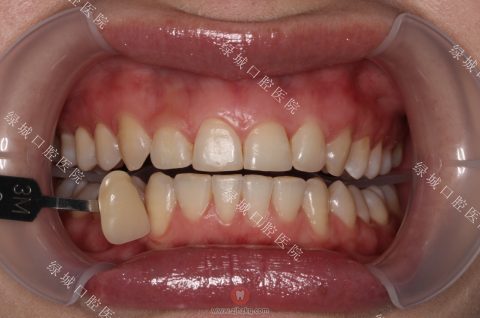

冷光美白操作时需涂蓝色的护龈树脂

大家最期待的一定是冷光美白的效果。用事实说话,这是我们冷光美白前后的对比,牙色在一定程度上变白,患者也比较满意。

四环色素牙冷光美白前